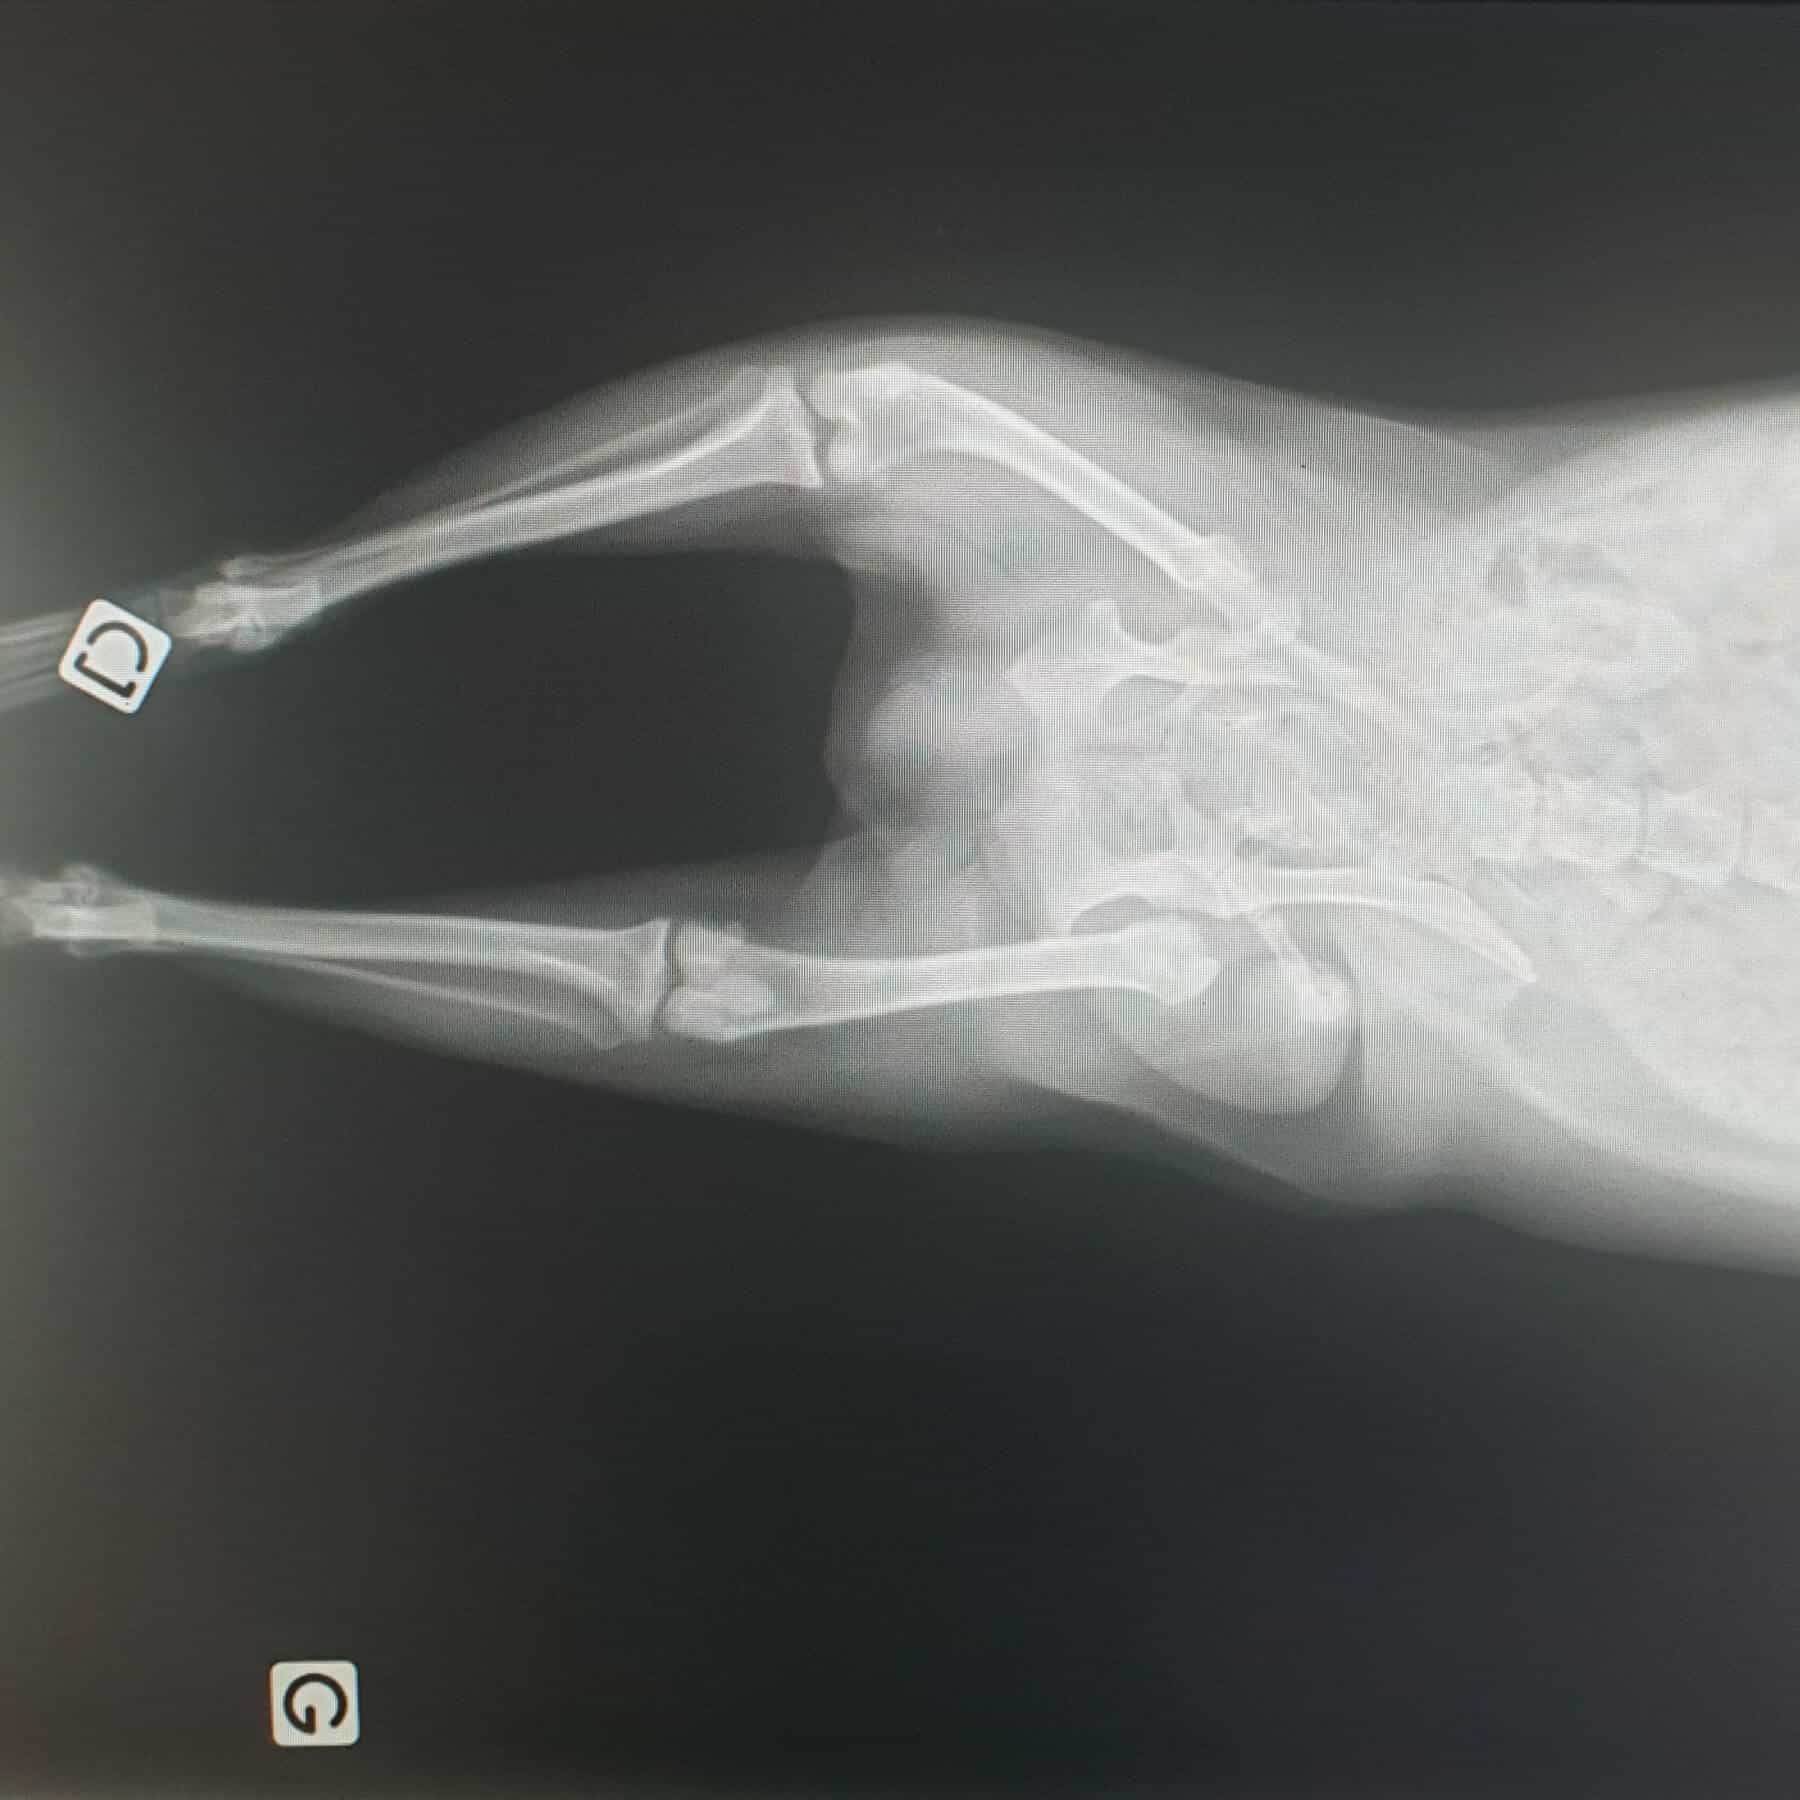

Radiographie

Nous disposons d’un appareil de radiographie numérique qui nous permet d’obtenir instantanément des clichés radiographiques permettant de diagnostiquer bon nombre de pathologies (osseuses, cardiaques, pulmonaires, tumorales…). L’examen est rapide et non traumatisant pour nos petits patients et fait parti des examens complémentaires de routine indispensables car d’une aide diagnostique précieuse. Tous les vétérinaires de la clinique sont formés à l’interprétation des clichés radiographiques.